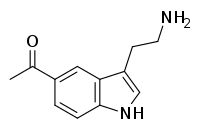

| Acetryptine | artificial | 5-COCH3 | H | H | 5-Acetyltryptamine | 3551-18-6 |